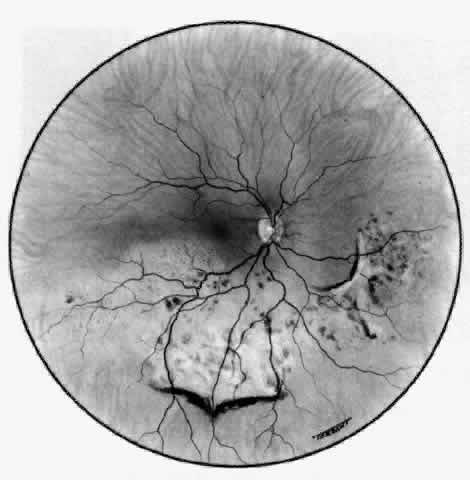

The characteristic features of necrotizing scleritis on fluorescein angiography are hypoperfusion and, eventually, nonperfusion of the vascular networks (Figs. 40 through 43).26 The initial changes are on the venous side of the capillary network; the transit time of the dye increases even if the eye is red and congested. If the disease process persists or has been present for a long time, thrombosis and permanent vaso-occlusive changes occur. These vessels (or the occluded capillary network) are bypassed by the opening of anastomotic channels. New vessels in a granuloma give rise to deep intrascleral leakage of dye (see Fig. 43). Conjunctival and episcleral involvement by the destructive change is late but is always preceded by vaso-occlusive changes that can sometimes be detected with use of the red-free light on the slit lamp (Figs. 44 and 45).

Fig. 40. Early necrotizing scleritis. There is characteristic yellow discoloration of the sclera underlying the conjunctiva at a point of necrosis. In this instance a small filament of tissue has penetrated the conjunctiva.

Fig. 41. Late stage of fluorescein angiogram adjacent to the site of necrosis in the same patient as in Figure 40. Although the eye is uniformly congested, the area near the necrosis shows vascular shutdown, whereas the rest of the conjunctiva and episclera is normally perfused.

Fig. 42. Late arterial phase of fluorescein angiogram in a patient with necrotizing scleritis. All the vessels except the main trunk and the vessels around the limbal perforating vessels are occluded and remain unperfused throughout the angiogram.

Fig. 43. Late venous phase of angiogram of a patient with necrotizing scleritis showing late deep leakage from vessels on the surface of the sclera and leakage of the capillary network at the limbus and the vessels draining it, together with poor or absent perfusion of the remaining vessels.